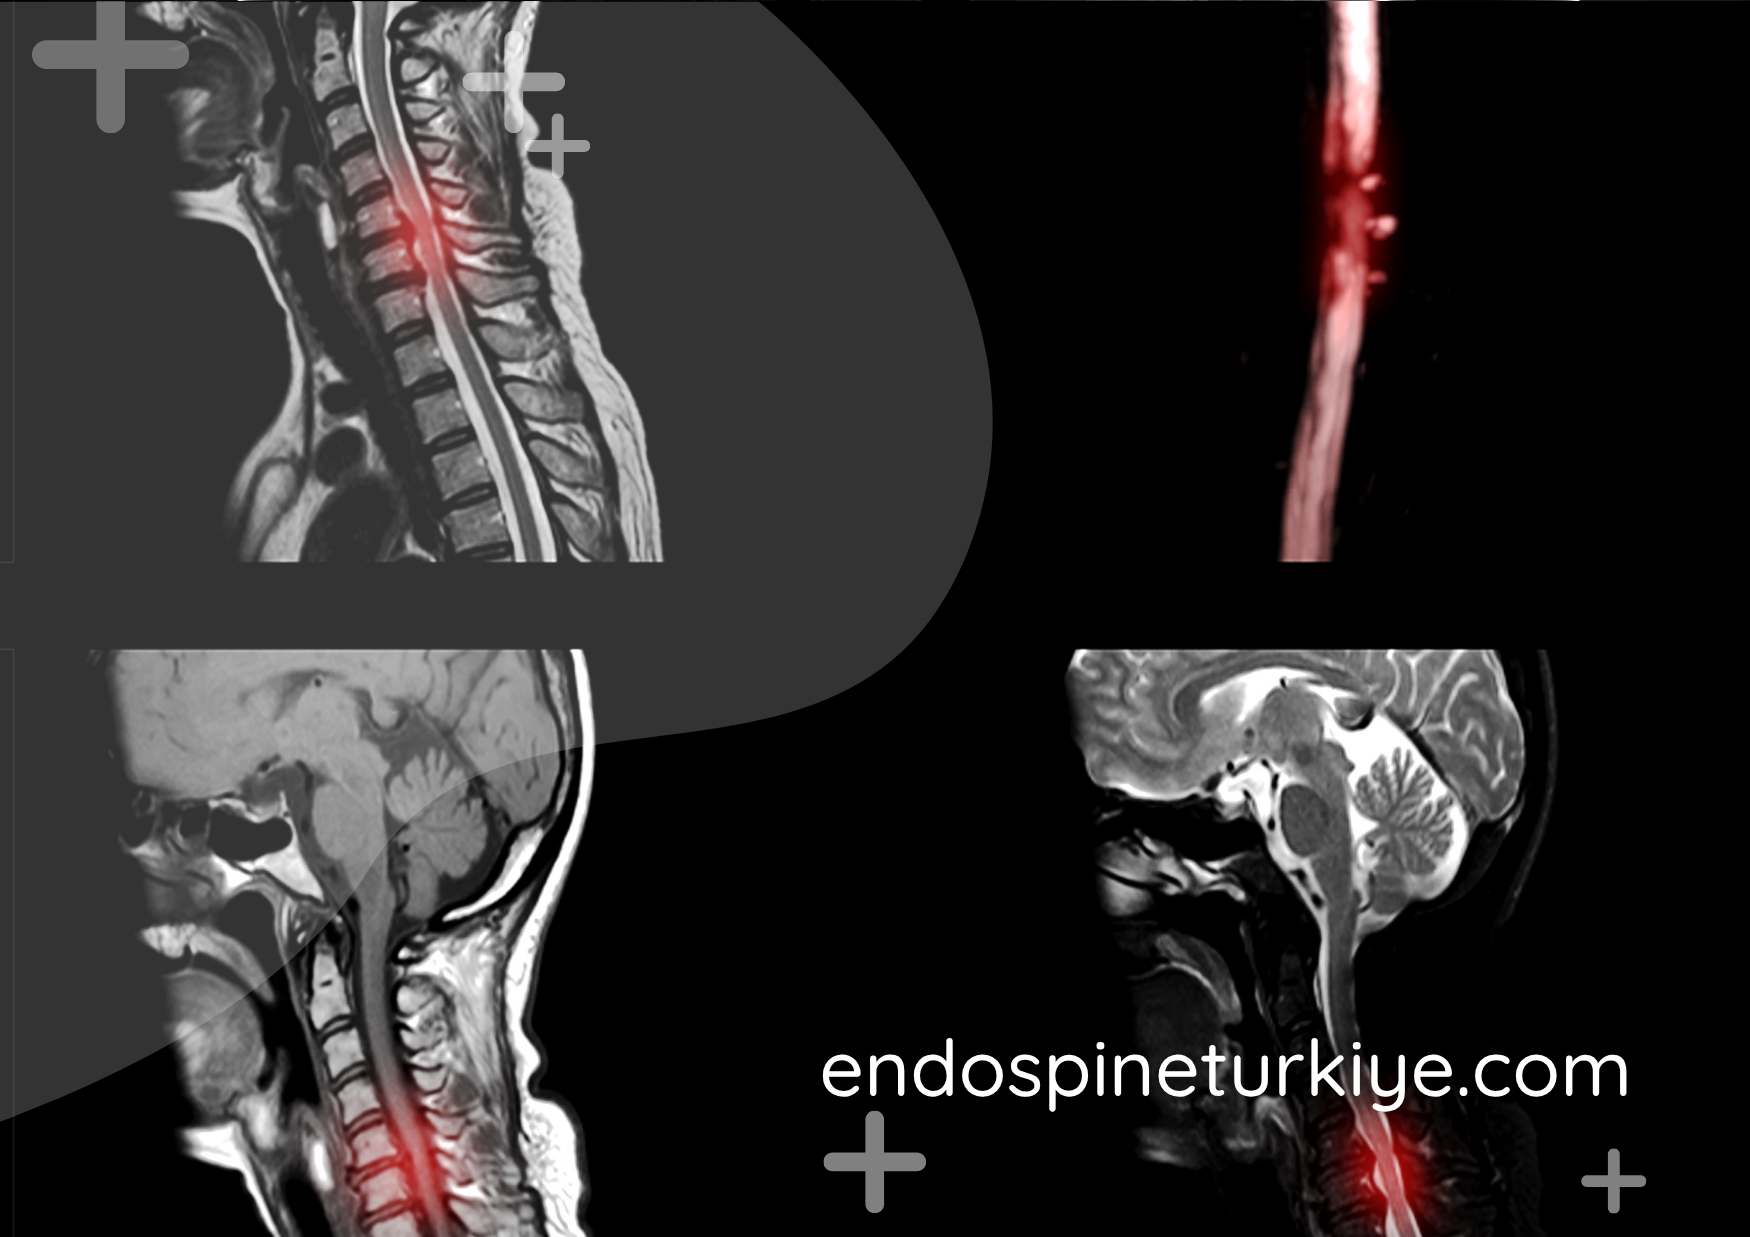

Boyun fıtığı MR görüntüsü - C5-C6 ve C6-C7 seviyeleri

Tam kapalı endoskopik boyun fıtığı ameliyatı, boyun omurgasındaki fıtık dokusunun HD endoskopik kamera sistemi kullanılarak minimal invaziv yöntemle çıkarılması işlemidir. Perkütan Endoskopik Servikal Diskektomi (PECD) olarak da bilinen bu teknik, boyun fıtığına kalıcı çözüm sunar.

6mm'lik minimal kesi ile gerçekleştirilen bu ameliyat, özellikle C5-C6 ve C6-C7 seviyelerindeki fıtıklarda yüksek başarı gösterir. Kol ağrısı, el ve parmaklarda uyuşma, güç kaybı gibi şikayetleri olan hastalarda tercih edilir. Klasik açık ameliyatlara göre çok daha az doku hasarı oluşturur ve füzyon (kaynatma) gerektirmez.